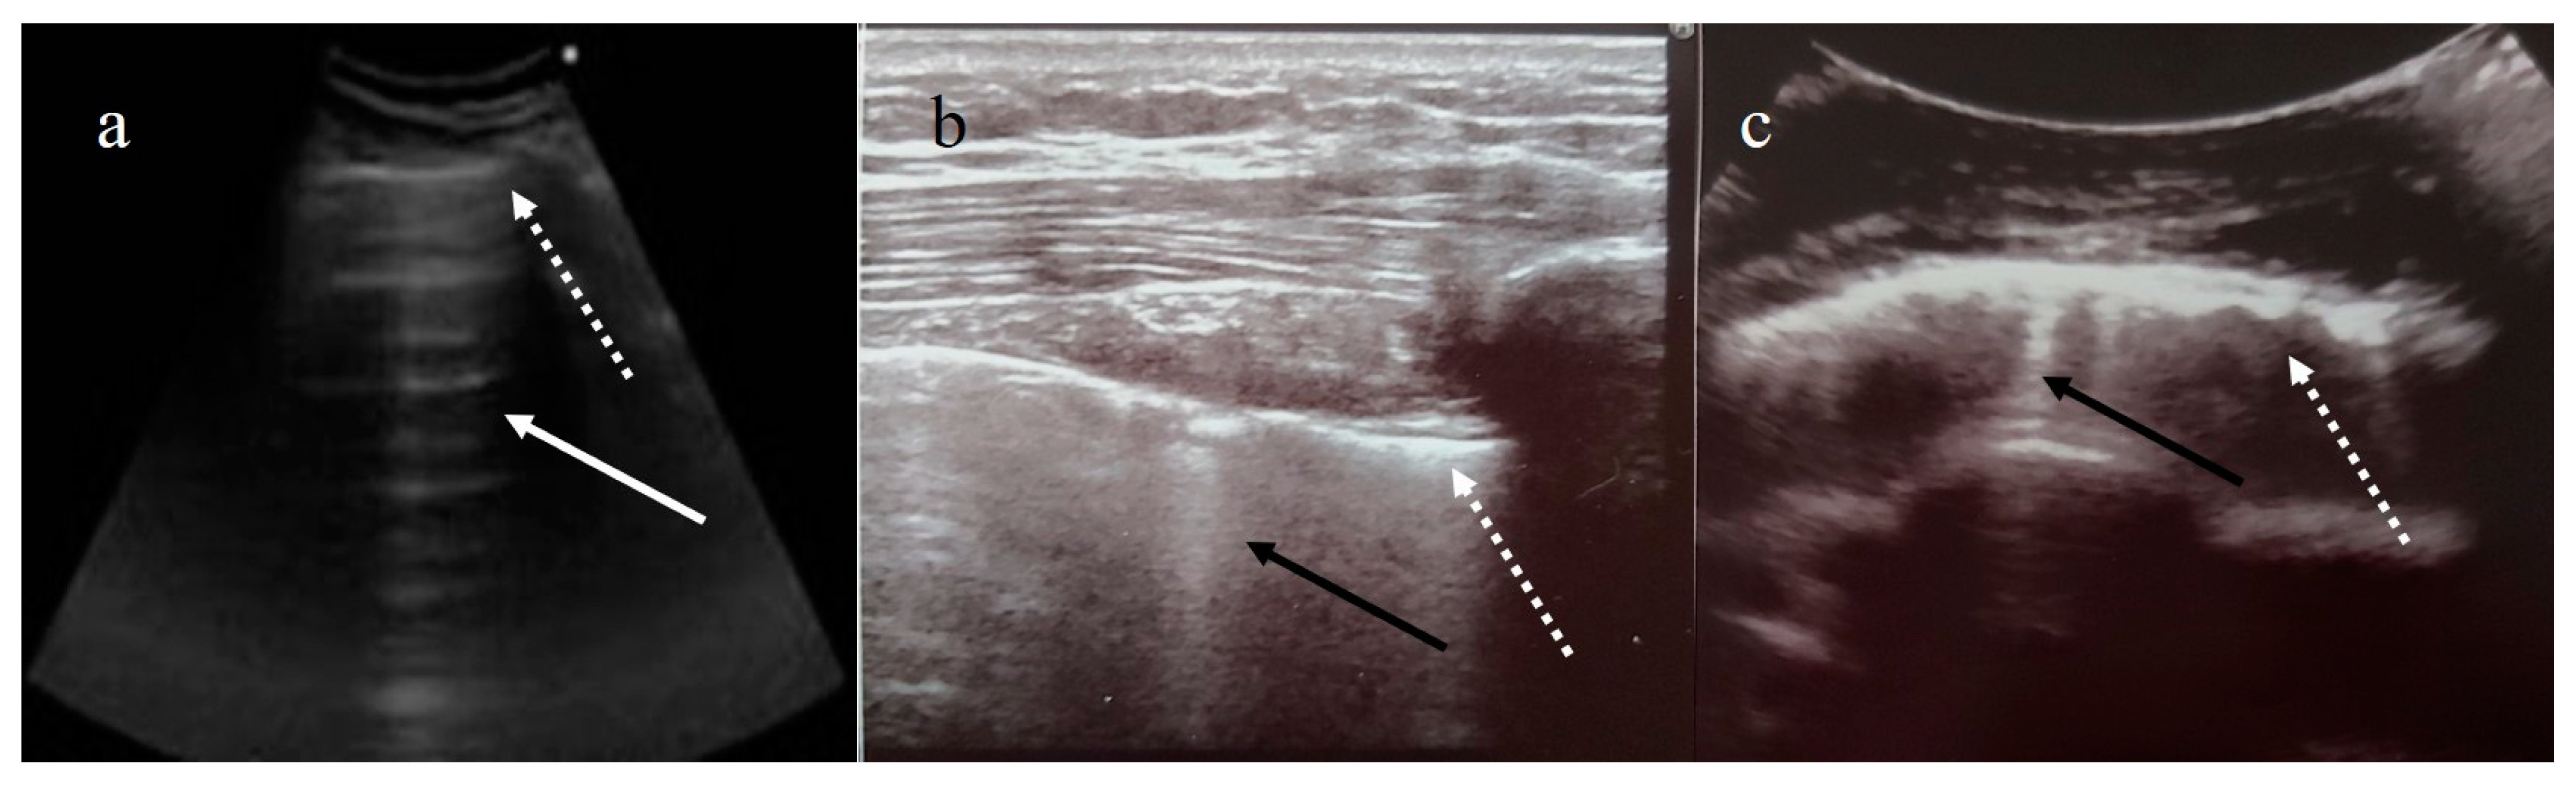

3. Lung Ultrasound

3.1. Lung Ultrasound: Role and Limitations

3.2. Lung Ultrasound: Protocols

3.3. Lung Ultrasound Scoring System